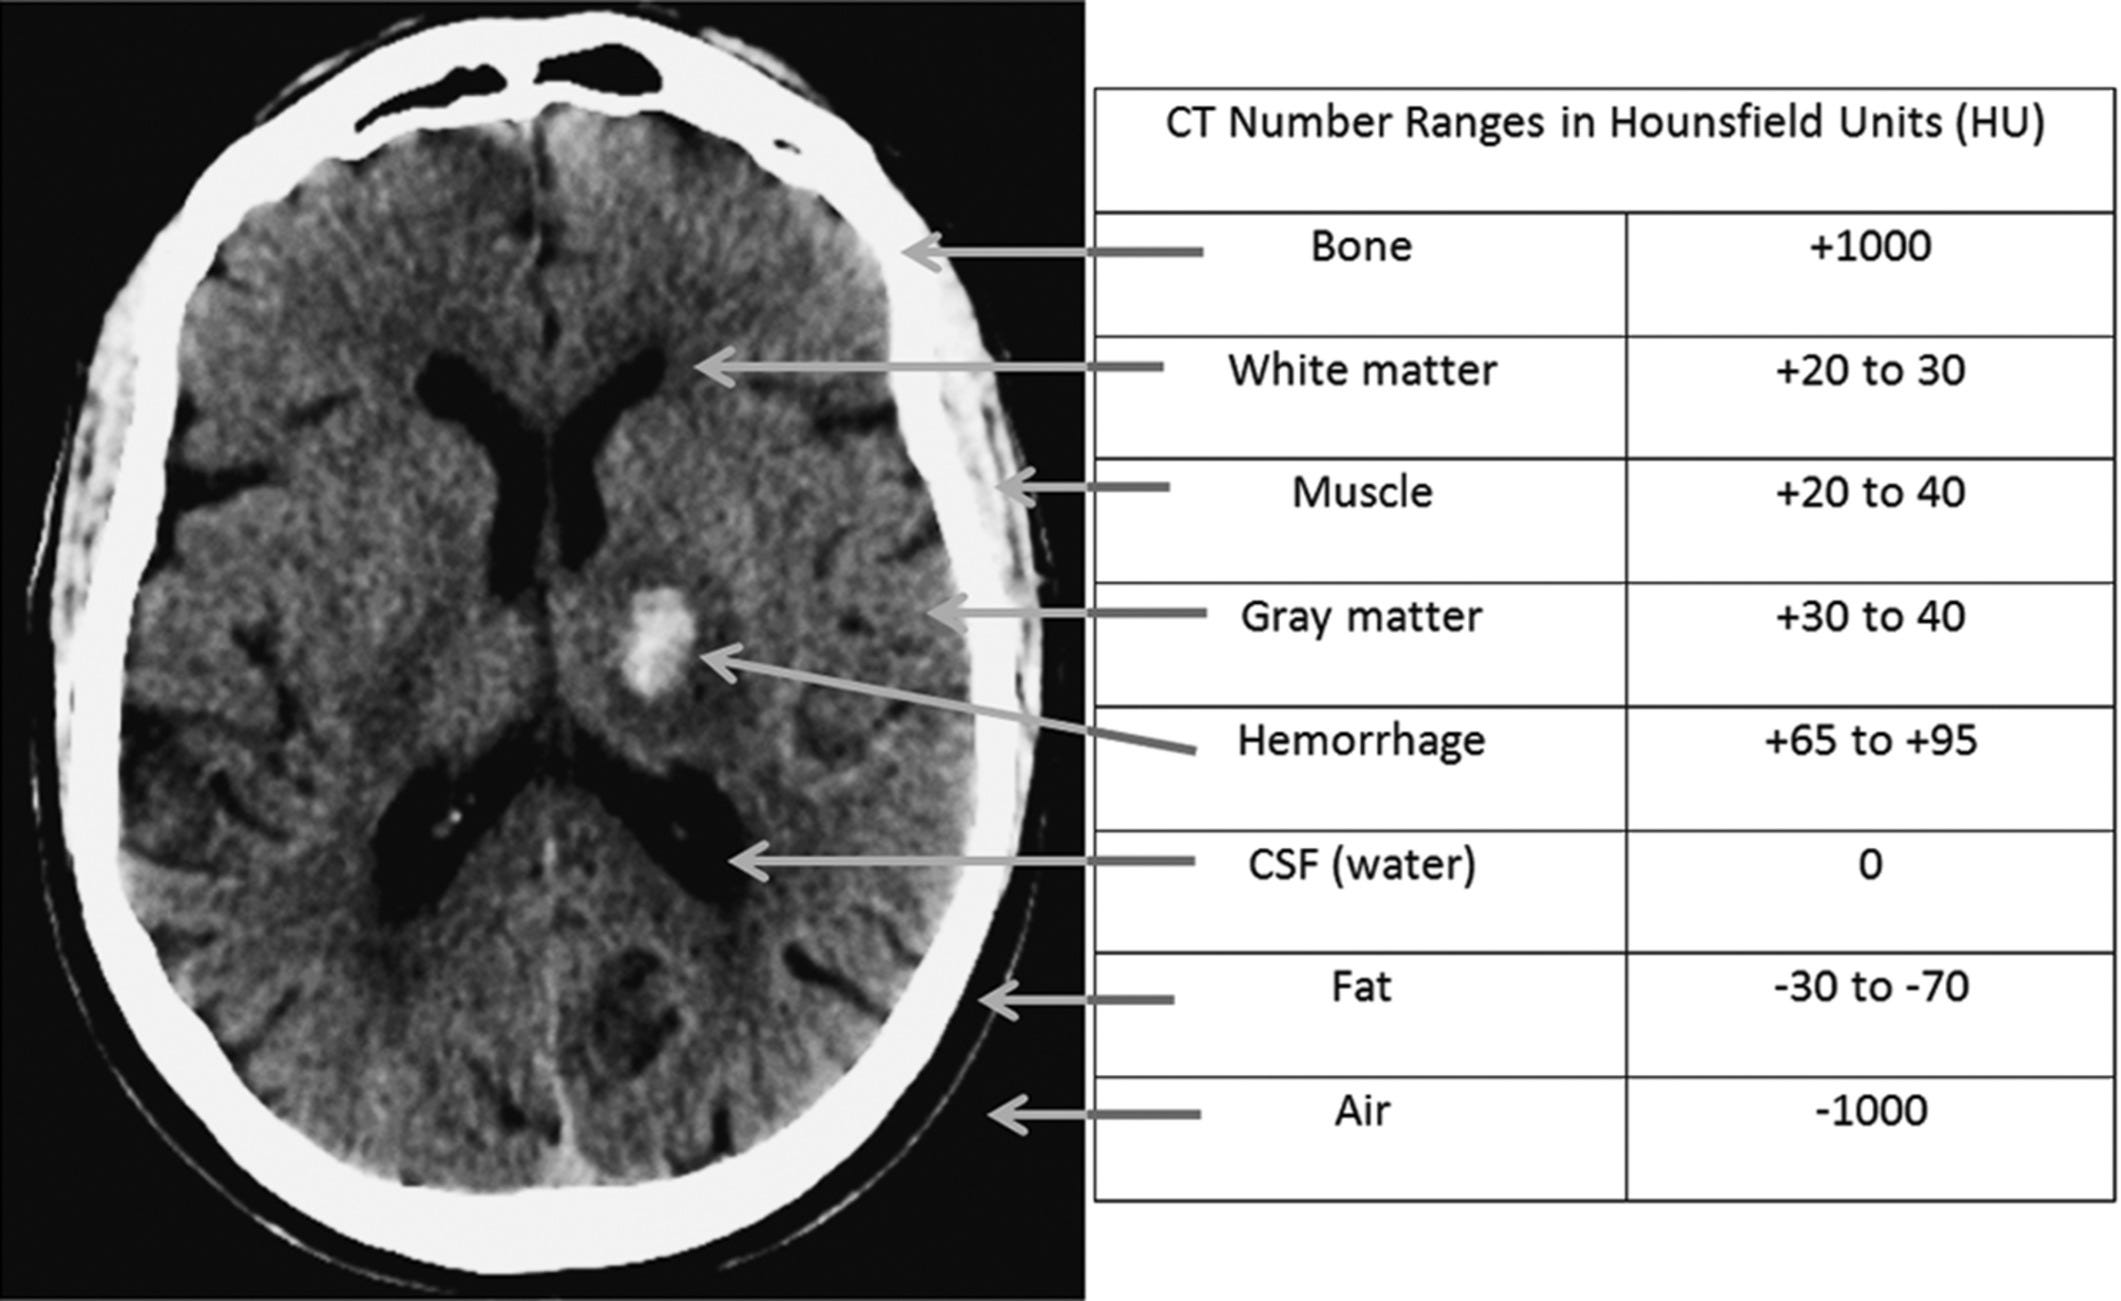

Ct Number In Ct Scan . Cnr = (ct vessel − ct soft. Hounsfield units (hu) are a dimensionless unit universally used in computed tomography (ct) scanning to express ct numbers in a standardized and convenient. High density tissue (such as. If the full ct number range of 2,000 (−1,000 to +1,000) is spread evenly over 200 discernible gray levels, each level represents a range of 10 ct numbers. The amount of attenuation is determined by the density of the imaged tissue, and they are individually assigned a hounsfield unit or ct number. Ct numbers based on measurements with the emi scanner invented by sir godfrey hounsfield 6, a nobel prize winner. However, it can be seen from. It is more precise to call this a. The hounsfield scale of tissue density is based on two values: Cnr is determined by the difference in ct numbers between vessel of interest and surrounding soft tissues in relation to the image noise:

Hounsfield units (hu) are a dimensionless unit universally used in computed tomography (ct) scanning to express ct numbers in a standardized and convenient. The amount of attenuation is determined by the density of the imaged tissue, and they are individually assigned a hounsfield unit or ct number. Ct numbers based on measurements with the emi scanner invented by sir godfrey hounsfield 6, a nobel prize winner. Cnr is determined by the difference in ct numbers between vessel of interest and surrounding soft tissues in relation to the image noise: It is more precise to call this a. However, it can be seen from. The hounsfield scale of tissue density is based on two values: If the full ct number range of 2,000 (−1,000 to +1,000) is spread evenly over 200 discernible gray levels, each level represents a range of 10 ct numbers. Cnr = (ct vessel − ct soft. High density tissue (such as.